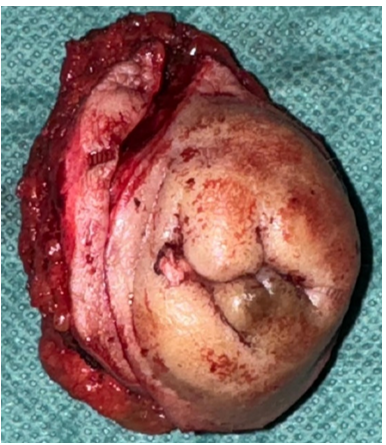

Thirty-eight-year-old patient, with two live children by caesarean section, consulting for Dysmenorrhoea and cyclic pelvic pain evolving for 6 months with, on clinical examination, an indurated mass measuring 4x3 cm opposite the external right side of the pfannestiel scar, pelvic ultrasound objectifying a deep, finely hypoechoic parietal nodular formation, measuring 32.7 x 12.7 mm, communicating with the pelvic cavity through a 4-mm diameter opening, suggesting an endometriotic nodule, followed on pelvic CT and MRI by a 35x20-mm nodular tissue mass of the rectus abdominis, suggesting parietal endometriosis (figure 1) associated with minimal subperitoneal endometriosis.

Figure 1.

Abdomino-pelvic CT scan showed an incisional supra-umbilical hernia with epiploic and uncomplicated digestive content, while pelvic MRI revealed soft-tissue nodules above and below the umbilicus, raising the initial suspicion of a parietal endometrioma (figures 3,4).

Figure 3-4: Soft tissue nodules above and below the umbilicus